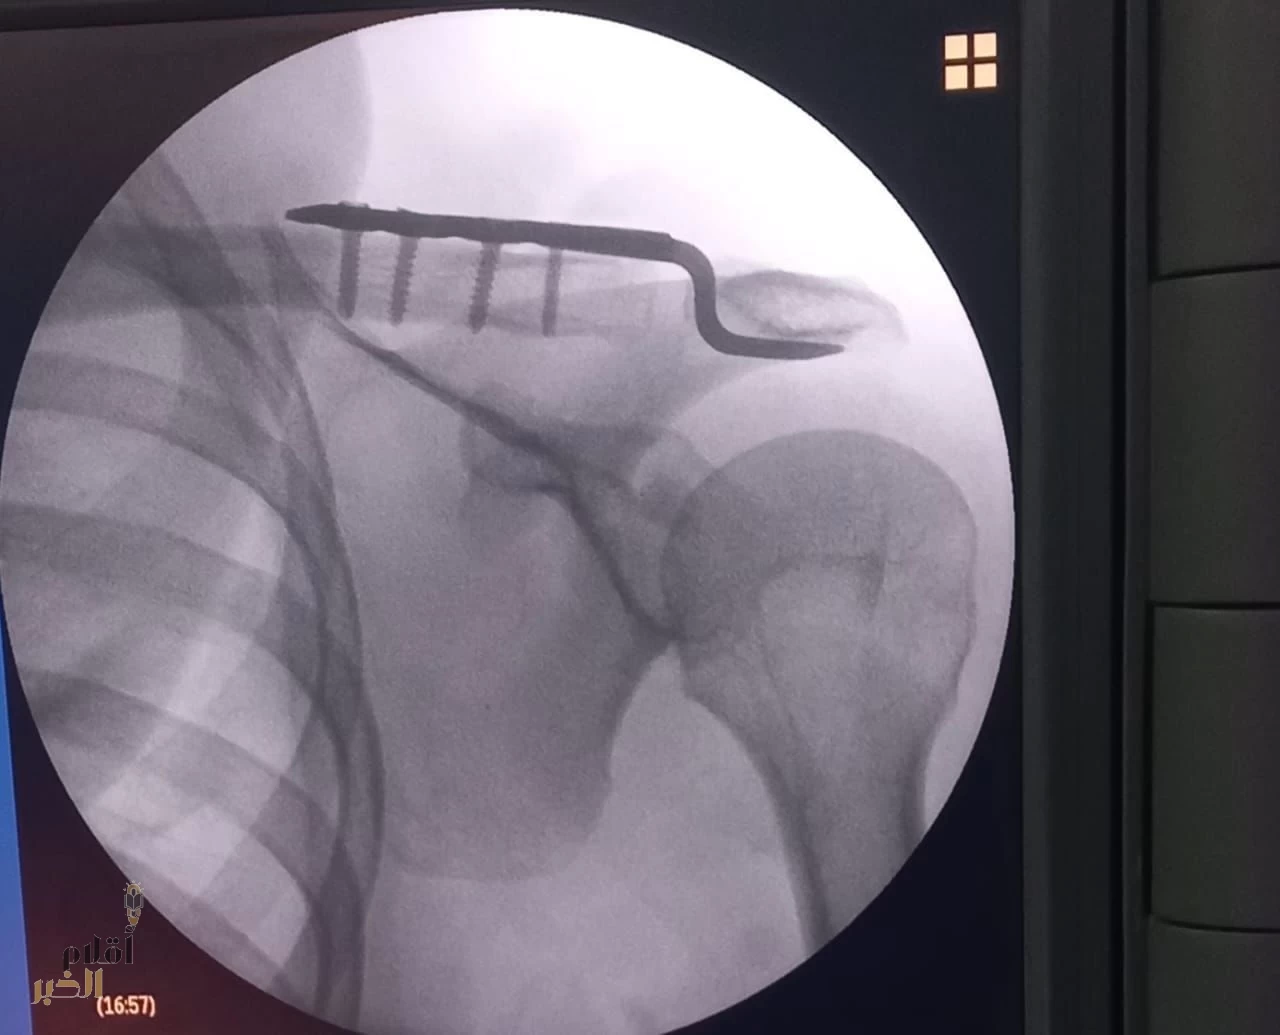

نجح فريق طبي في قسم جراحة العظام بمستشفى القويعية، عضو تجمع الرياض الصحي الأول، في إجراء عملية نوعية تُنفذ لأول مرة بالمستشفى، تمثلت في ردّ مفتوح لخلع بالمفصل الأخرمي الترقوي وتثبيته باستخدام شريحة خطافية، لمريض كان يعاني من خلع حاد من الدرجة الخامسة.

وأوضح استشاري جراحة العظام وقائد الفريق الطبي، الدكتور أحمد النجار، أن المريض خضع لسلسلة من الفحوصات الطبية والمخبرية والأشعة التشخيصية اللازمة قبل إجراء العملية، والتي تكللت – ولله الحمد – بالنجاح، حيث تم ردّ المفصل الأخرمي وتثبيته بالشريحة الخطافية وفق أحدث المعايير الجراحية.